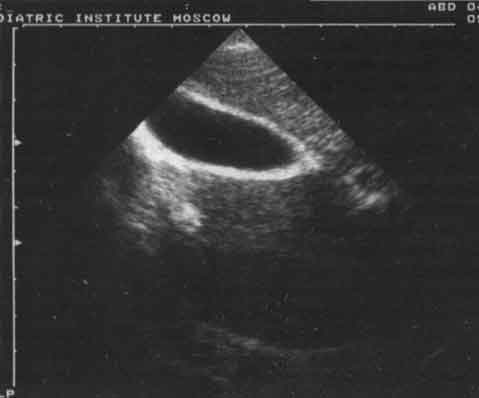

Изменения желчного пузыря были представлены в основном нарушением его формы - перегибы в области дна, тела (21%), S-образные перегибы (9%) и наличие перегородок и перетяжек (7%). У 12% детей имело место увеличение желчного пузыря, у 8% - утолщение стенок более чем на 2 мм, что является ультразвуковым признаком холецистита. У 0,5% детей в просвете пузыря были выявлены конкременты, размер которых не превышал 6 мм, из них у 82% они не были кальцинированы. Этот вывод был сделан на основании отсутствия "дистальной тени" за эхосигналом от конкремента. Оценка сократительной функции желчного пузыря позволила в 83% случаев выявить ее нарушение, причем в 71% из них оно носило гипомоторный характер. В ряде случаев перечисленные отклонения в состоянии желчного пузыря были смешанными. Чаще всего наблюдалось сочетание аномалий с увеличением желчного пузыря (рис. 3 - 5).

Рис. 3. Эхограмма желчного пузыря с S-перегибом.

Рис. 4. Эхограмма желчного пузыря при хроническом холецистите.

Рис. 5. Эхограмма желчного пузыря с конкрементом (обозначен стрелкой).